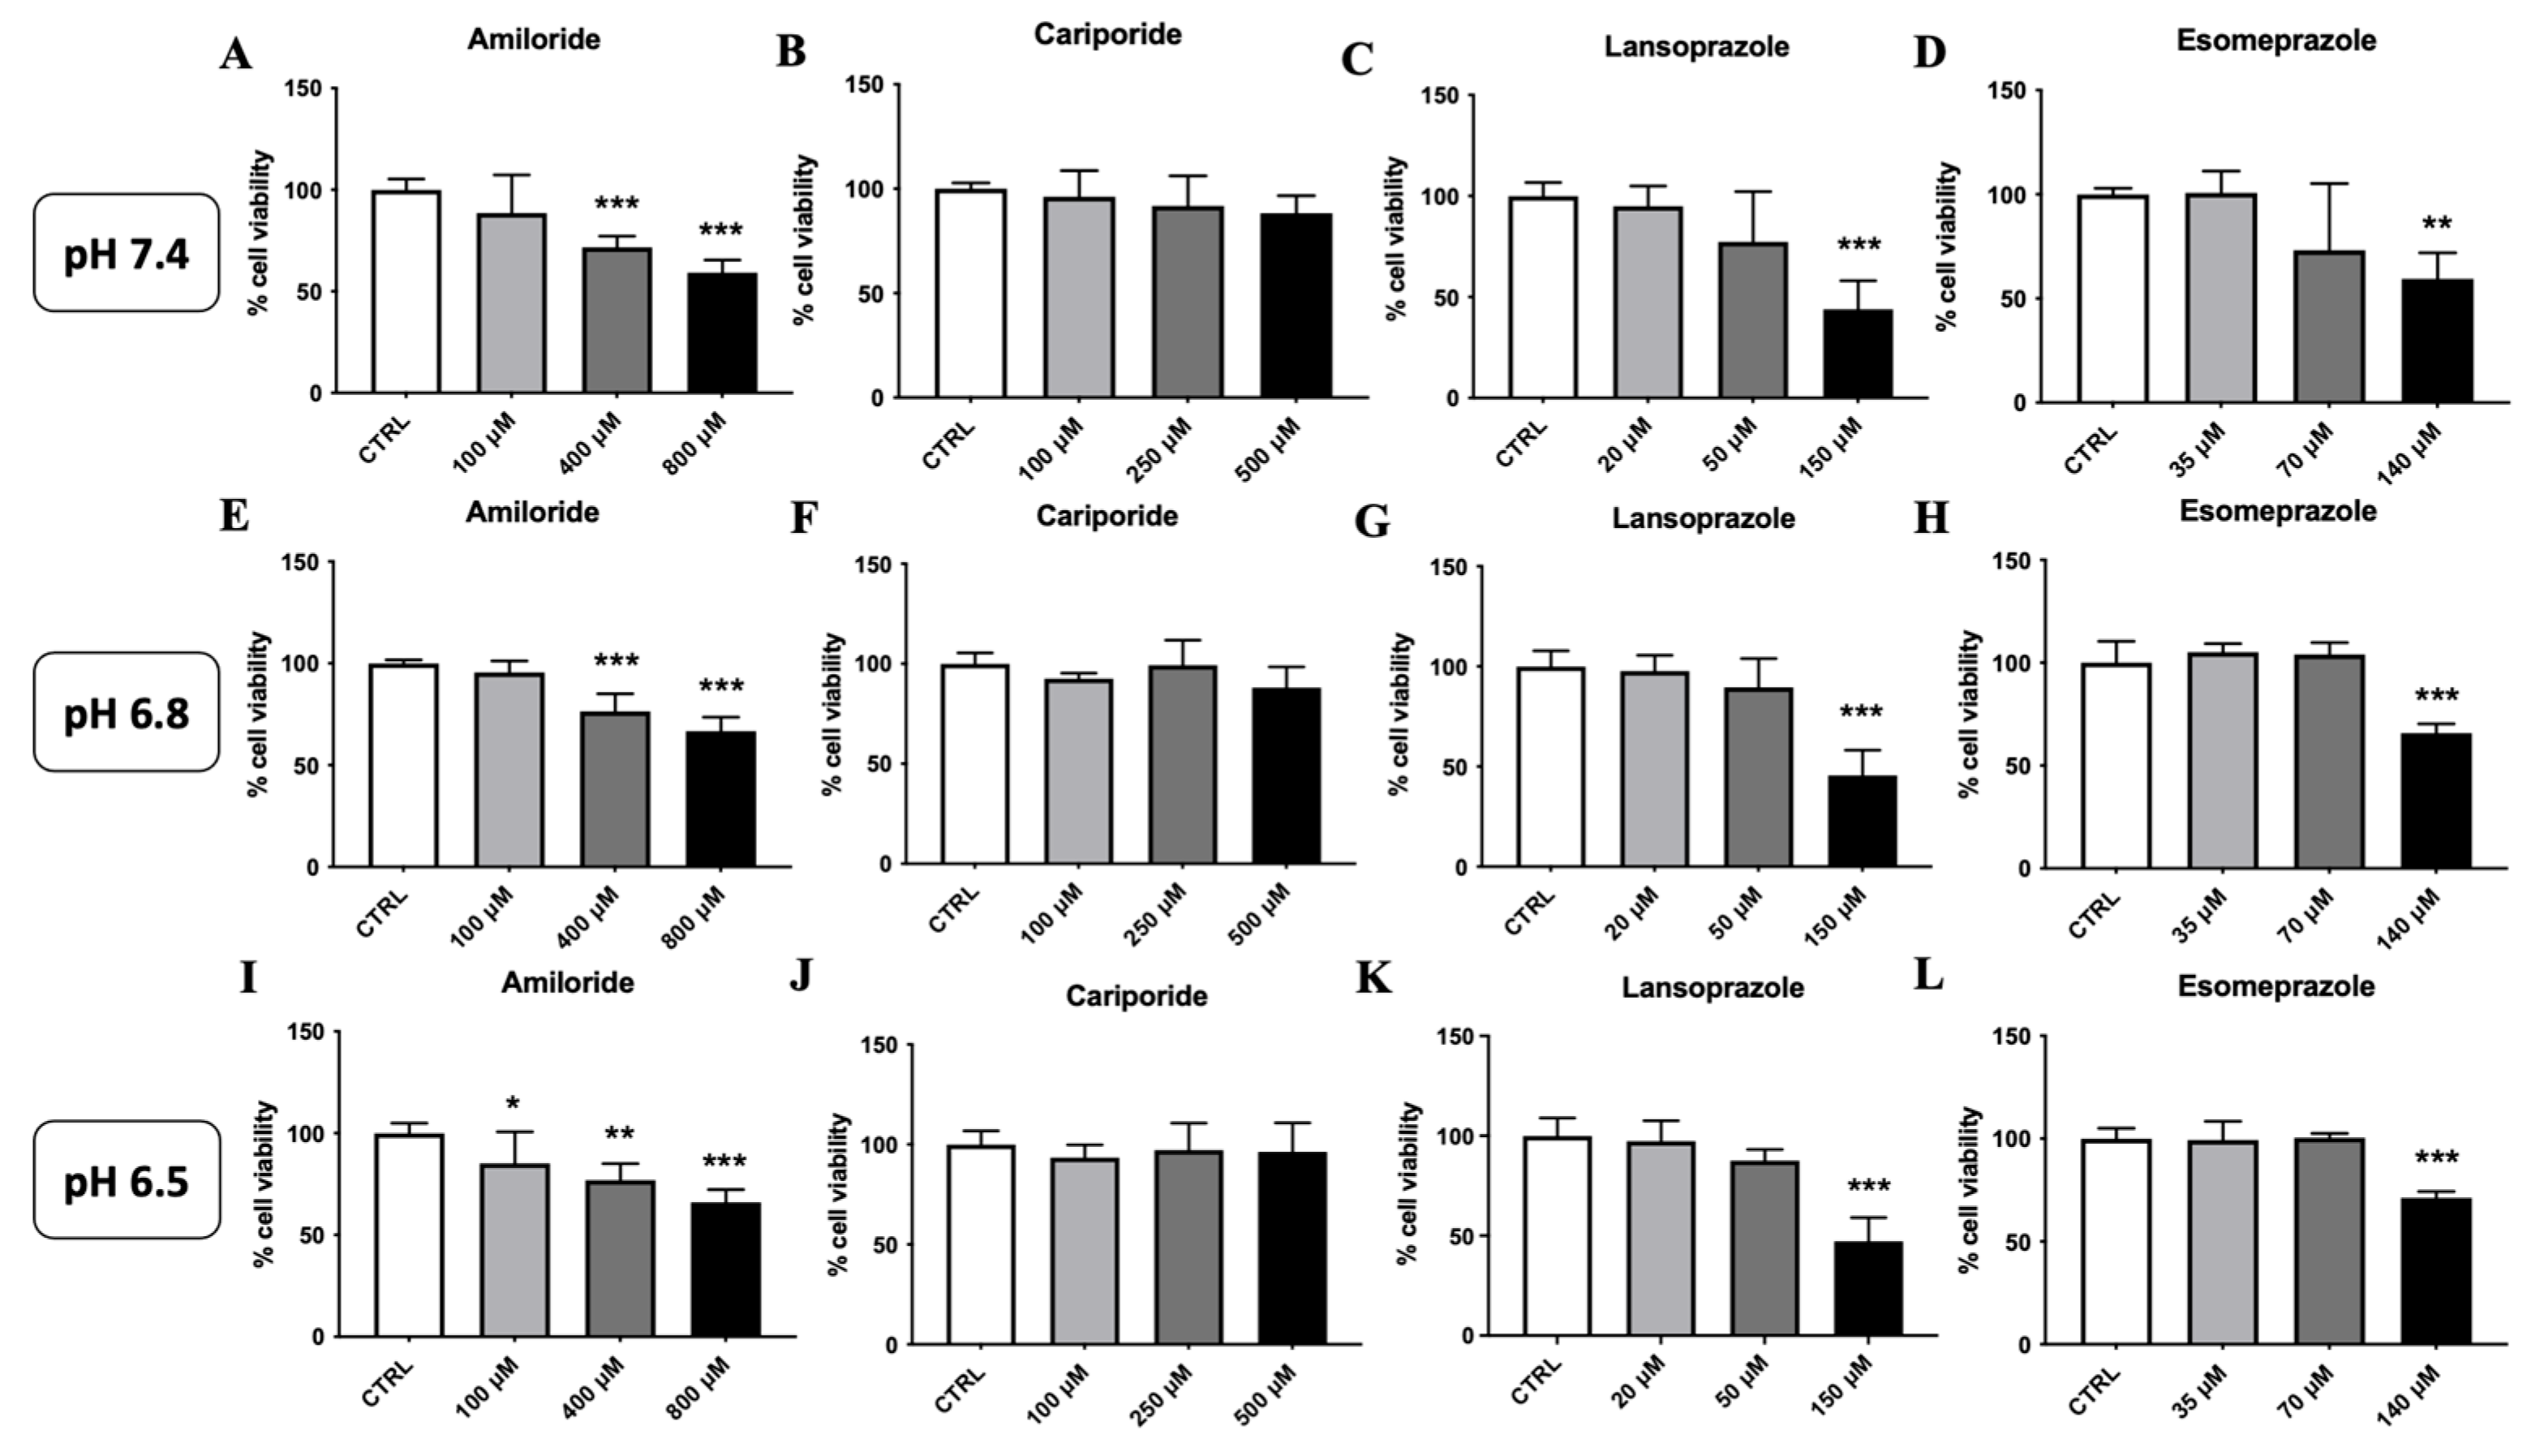

2.3. Cell Proliferation/Cell Viability Assay

3.1. Lansoprazole and Amiloride Halt Cell Proliferation in 4T1 Metastatic Breast Cancer